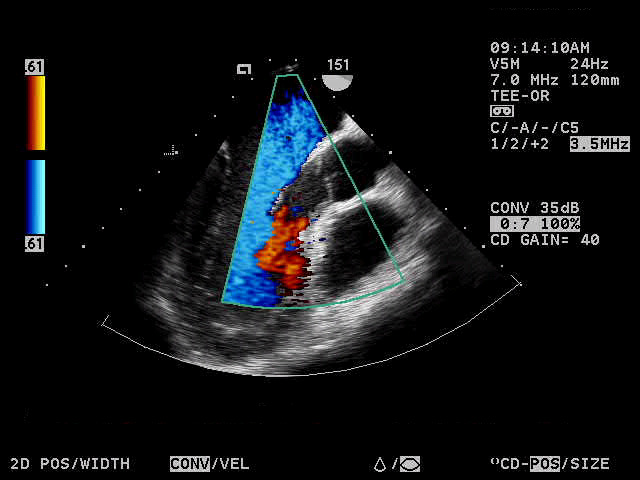

While the Doppler ultasound test is performed, you will hear a swishing sound as the instrument receives and processes the signals. Doppler ultrasound is particularly helpful in the evaluation of heart murmurs. Color ultrasound imaging provides additional information about direction and distribution of blood flow. When this is being performed, you will notice multiple colors on the monitor screen.

The echocardiogram test includes Doppler and color

evaluations of your heart.